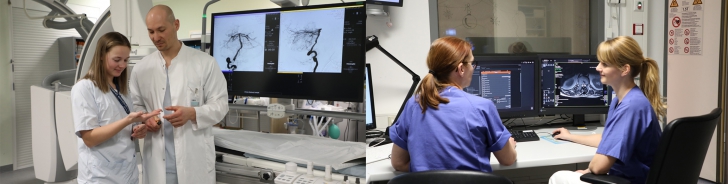

Neuroradiology is your contact partner for diagnostics and minimally invasive therapy of diseases and changes of the nervous system, i.e. of the brain and spinal cord, peripheral nerves and the immediate adjacent structures (e.g. the spine).

Diagnostically and therapeutically, the most modern methods and equipment are available for our patients. In addition to diagnostic neuroradiology, our clinic is characterized by a high level of expertise in minimally invasive neuroradiological therapy, both in the emergency treatment of strokes and in the elective treatment of aneurysms, vascular stenoses and vascular malformations.